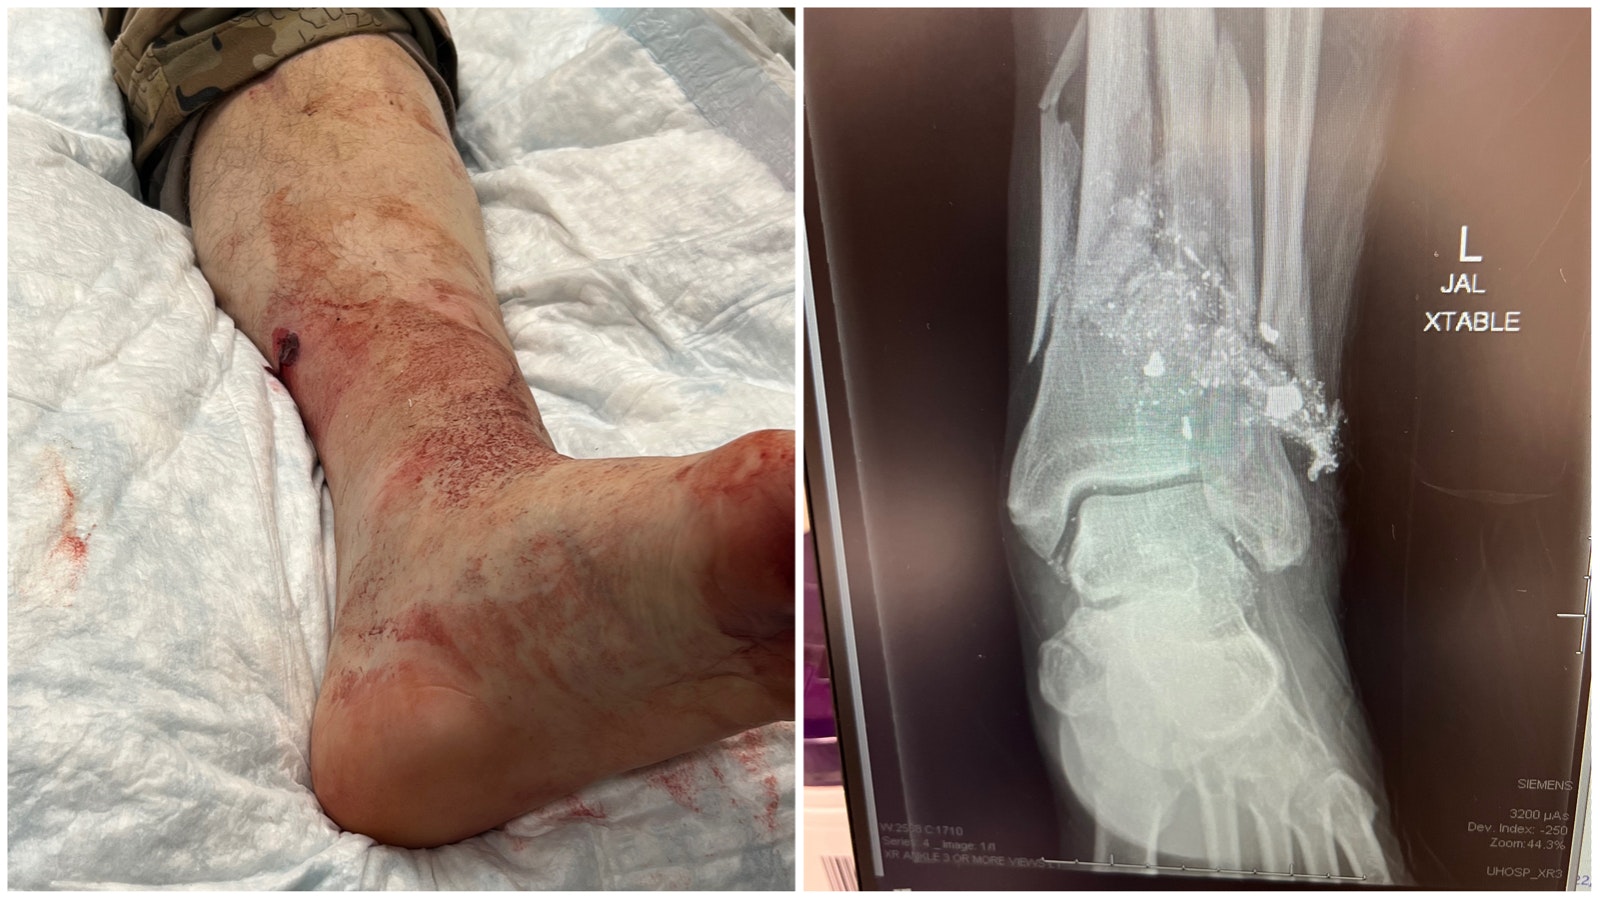

Despite Shooting Himself, Wyoming Hunter Says Handgun Saved Him From Grizzly

Evanston hunter Lee Francis told Cowboy State Daily that despite shooting himself, his 10 mm Glock saved his life. "The grizzly was a foot away from the muzzle and it was just bam, bam, bam, bam, bam!"